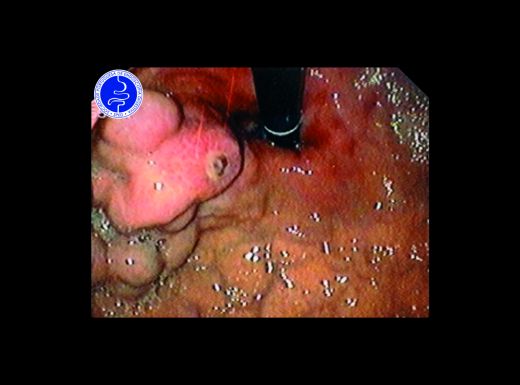

Parasitose gástrica

- Estômago